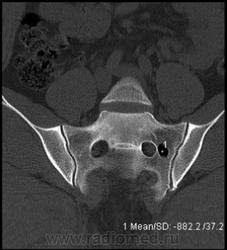

Случай 2: Внутрикостная пневмоцистика

Внутрикостная пневмоцистика